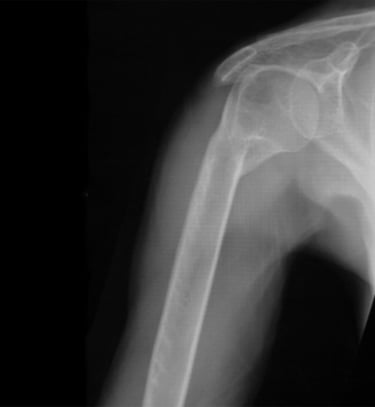

Gydytojas Markas Fiodorovas - ortopedas traumatologas, sporto traumų specialistas, sukaupęs 20 metų patirtį tausojančioje artroskopinėje chirurgijoje. Daugiau nei 650 artroskopinių kelio, peties ir kitų sąnarių operacijų per metus atliekantis chirurgas, taip pat aktyviai įsitraukęs į mokslinę veiklą. Gydytojas yra nuolatinis tarptautinių konferencijų lektorius bei tarptautinis artroskopinės chirurgijos instruktorius.